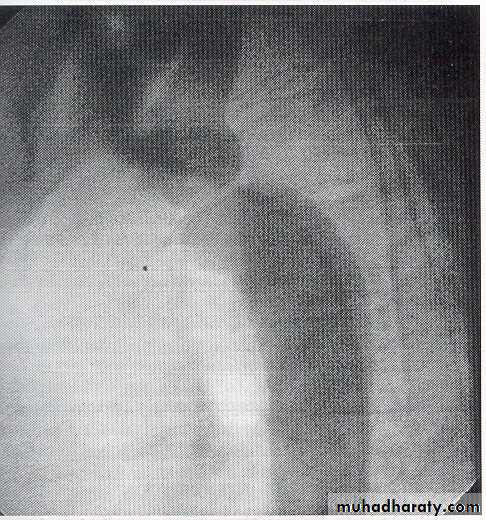

Investigations

Chest X-ray in early childhood is often normal but later may show changes in the contour of the aorta (indentation of the descending aorta, ‘3 sign’) and notching of the under-surfaces of the ribs from collaterals.

"pre-stenotic and post-stenotic dilatation to form “3” shape"